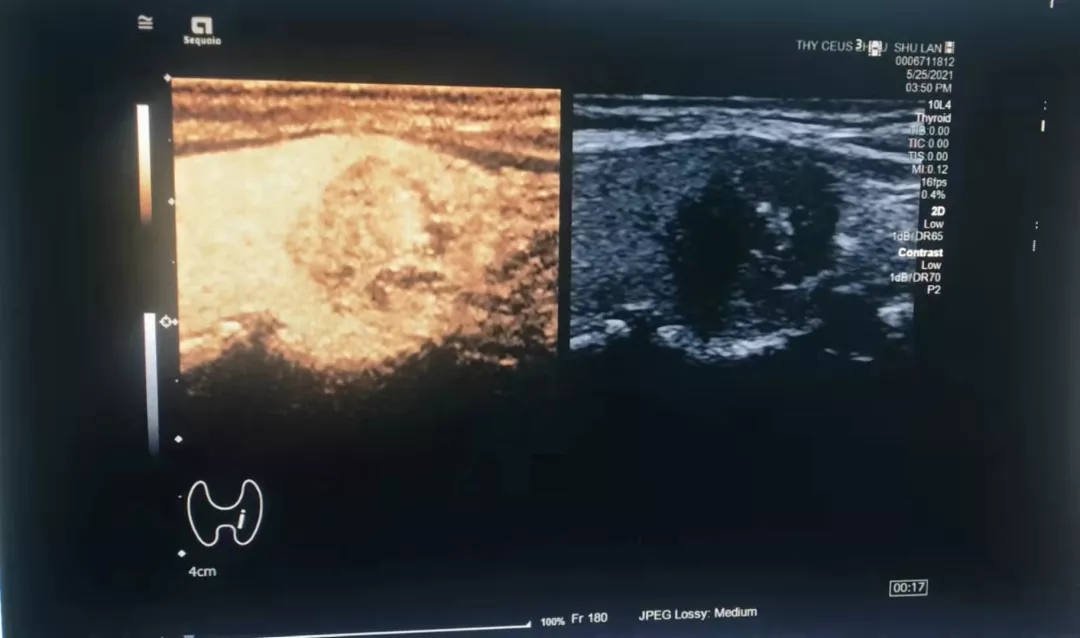

图为开展的甲状腺超声造影检查

超声造影技术的临床应用如下: